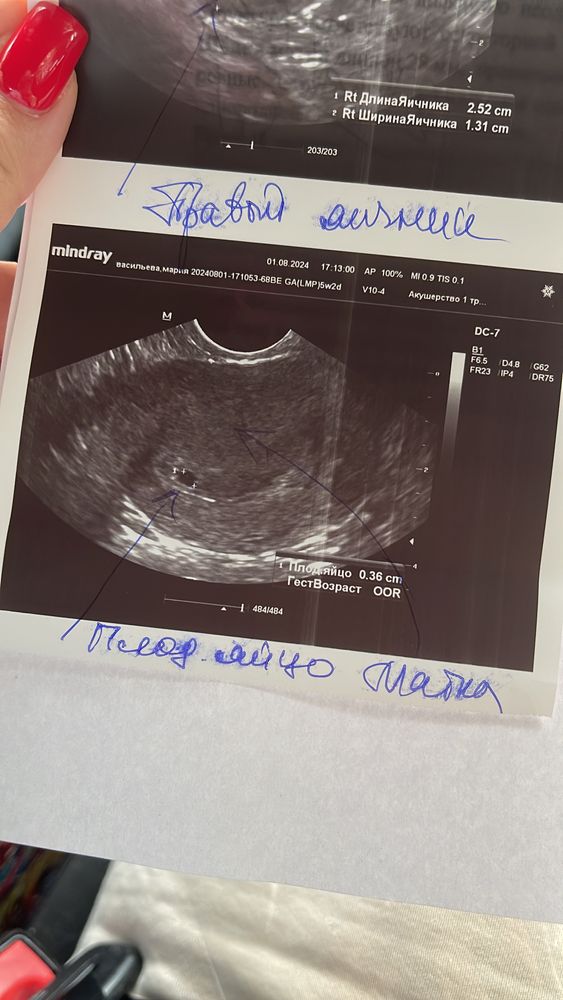

ИзображениеВот что было у меня в 5 недель

Анастасия, пя- 9,2

Анастасия, по пм 9.6